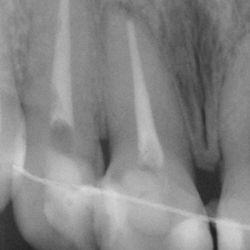

Το 9χρονο αυτό κοριτσάκι έσπασε τους κεντρικούς άνω τομείς μετά από πτώση στο έδαφος.

Τα δόντια απονευρώθηκαν και στη συνέχεια αποκαταστάθηκαν με συνδιασμό τοποθέτησης ενδοριζικών αξόνων και ανασυστάσεων σύνθετης ρητίνης.

Συγκεκριμένα, άξονες υαλονημάτων τελευταίας τεχνολογίας (ParaPost FiberWhite/Coltene και FiberCone/RTD) συγκολλήθηκαν εντός των ριζών και τα δόντια ανασυστήθηκαν με νανουβριδική σύνθετη ρητίνη (Herculite XVR Ultra/Kerr) με την βοήθεια ειδικής μήτρας/οδηγού από σιλικόνη.

Το χαμόγελο της μικρής ασθενούς μας αποκαταστάθηκε άμεσα όπως είναι εμφανές στην τελευταία φωτογραφία.